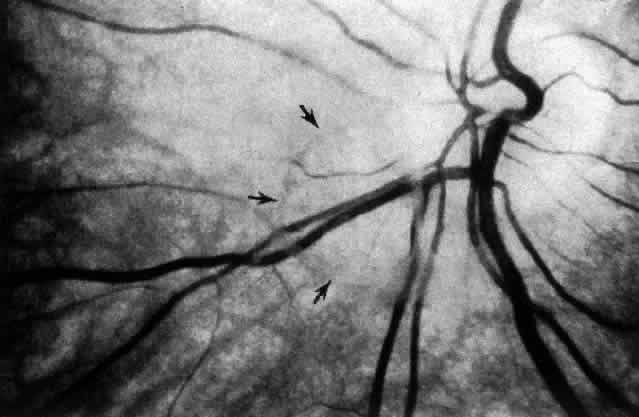

SURGICAL ANATOMY OF PROLIFERATIVE DIABETIC RETINOPATHY

Proliferative Diabetic Retinopathy (PDR) results from migration and proliferation of vasoformative cells from the retina and optic disc in response to angiogenic stimuli.201–203 As the disease progresses, these vessels continue to grow out of the retinal plane, along and/or into the posterior vitreous cortex (Fig. 18). Fibrovascular membranes excised from patients with PDR contain type II vitreous collagen in nearly all cases studied histopathologically.141 Thus, the position of the posterior vitreous cortex relative to the retina can influence the course of PDR in a number of ways. Jalkh and co-workers204 have noted that diabetic patients with a totally detached posterior vitreous have the lowest risk of a progression in the severity of their retinopathy. Those with a partially detached vitreous have the highest risk of progressing to more severe PDR. Since new vessels grow into the vitreous cortex, any displacement of the corpus vitreous due either to trauma, vitreous detachment, or osmotic fluxes would transmit traction to the new blood vessels.